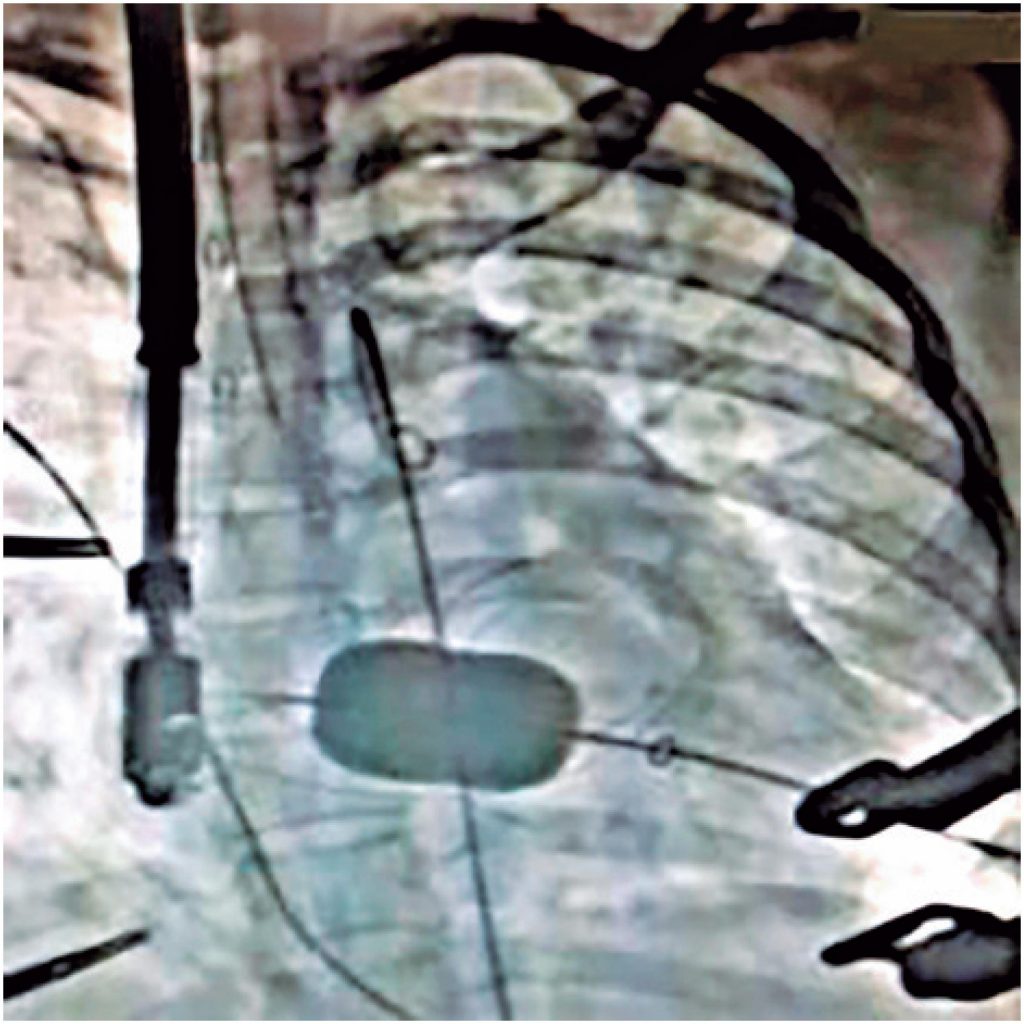

Este relato descreve uma alternativa terapêutica para a correção de estenose mitral grave determinante de fibrilação atrial de alta resposta e consequente síncope em gestante de 8 semanas. Houve insucesso em valvuloplastia percutânea, pela impossibilidade de punção do septo atrial e subsequente resolução definitiva com valvoplastia transapical, por toracotomia em janela inframamária esquerda, com acesso direto à valva mitral. Sendo um procedimento original e de complexidade, este caso apresenta relevante importância no tratamento de estenose mitral grave em pacientes cujas condições impossibilitam o procedimento convencional.